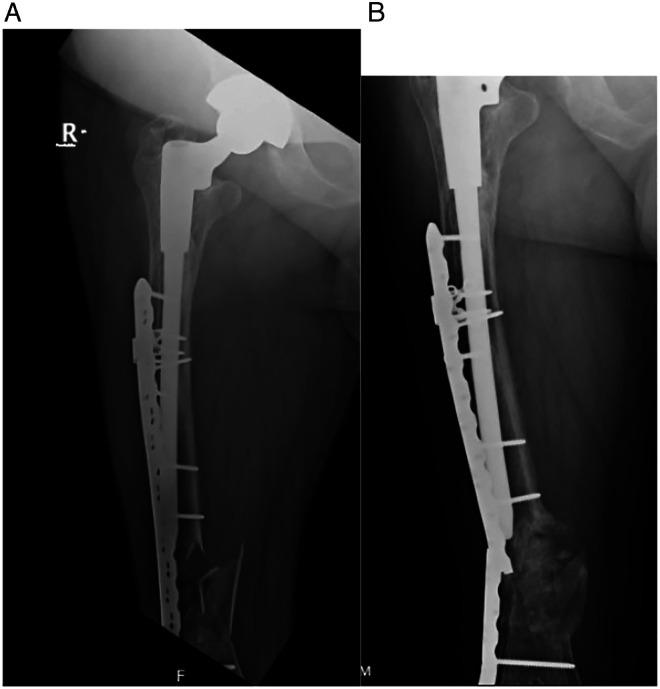

The locking attachment plate (LAP) can be added to a locking compression plate (LCP) to allow the fixation of locking screws bicortically around a femoral implant. We aimed to examine surgical and fracture characteristics associated with healing for periprosthetic femur fractures (PPFFx) treated with constructs employing LAP fixation. We hypothesize that the addition of an LAP provides stable peri-implant fixation.

MATERIALS &METHODS: We retrospectively reviewed a consecutive series of 28 PPFFx surgically treated with LCP-LAP constructs by 4 surgeons from 2015-2020. Fractures were classified and grouped using the Vancouver Classification System and included 12 B1, 2 B2, 11 C fractures, and 3 fractures around other stemmed implants. Primary outcome measures included hardware failure such as screw pullout, broken screws, and plate fracture. Clinical complications including infection, non-union, malunion, and reoperation were recorded.

No LAP failures, screw pullout, or broken screws were observed. Two fractured plates (7.1%) occurred in patients with Vancouver C fracture types. Overall complication rate was 17.9% and included 3 non-unions, 1 deep infection, and 1 implant loosening with painful hardware, each requiring reoperation. Differences were observed between unions and nonunions for total number of screws (12.4 vs 14.7, = .005) and number of locking screws used (8.04 vs 11.3, = .03).

The LAP provides adequate fixation and low failure rates where fixation is required around a well-fixed stem. When failures occur, it is from plate breakage and not due to failure of fixation at the area of plate-stem overlap.